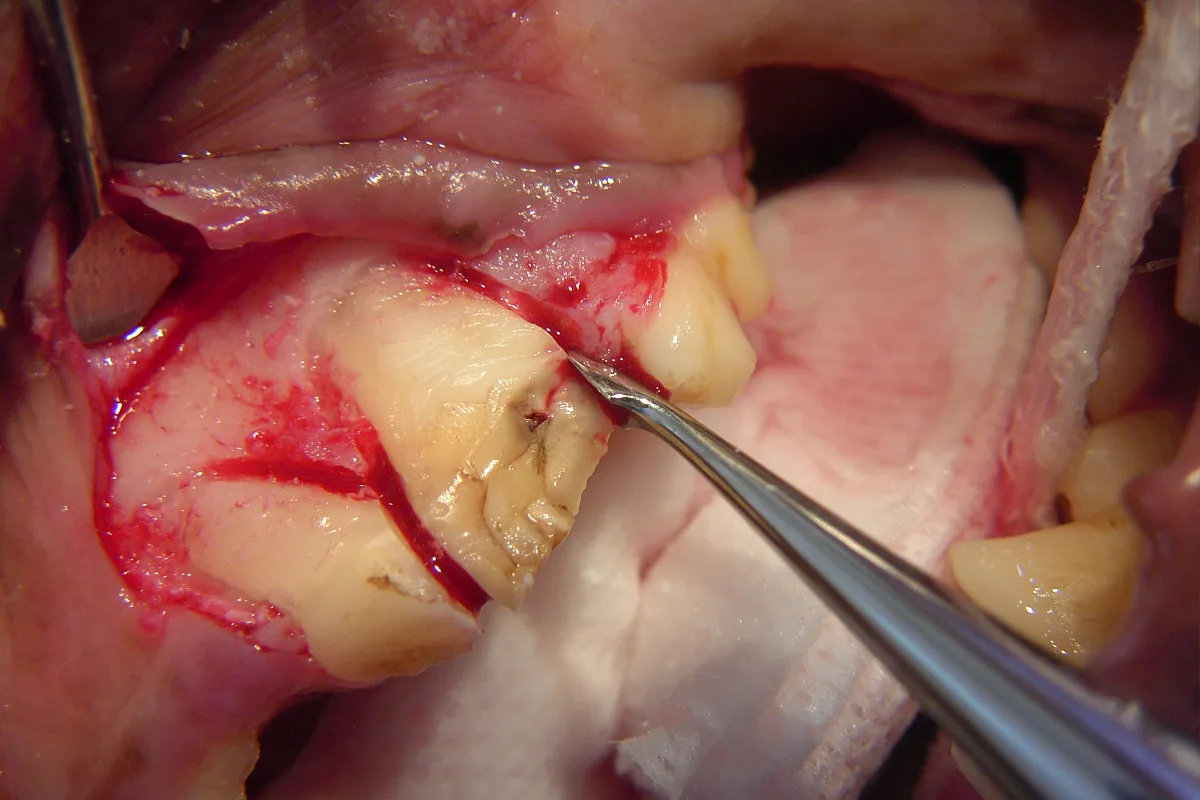

Step 3

A #4 Molt periosteal elevator is used to reflect the full thickness mucoperiosteal flap and expose the buccal alveolar bone. This reflection can stop at the mesiobuccal line angle of the maxillary 1st molar (just caudal to the tooth being extracted) or, if needed, it can continue over the buccal aspect of the maxillary 1st molar to the distobuccal line angle. The result will be a triangular gingival flap that should be well suited for coverage of the triangular defect created when the tooth roots are extracted.

Step 4

The buccal alveolar bone is removed using a round ball bur (#2, surgical length, friction grip) in a water-cooled, high-speed handpiece. The amount removed will depend on the experience and skill of the operator, but removing the alveolar bone to expose 25% to 50% of the buccal root surface should suffice. The removal of alveolar bone is guided by palpation and visualization of the alveolar juga of each root.